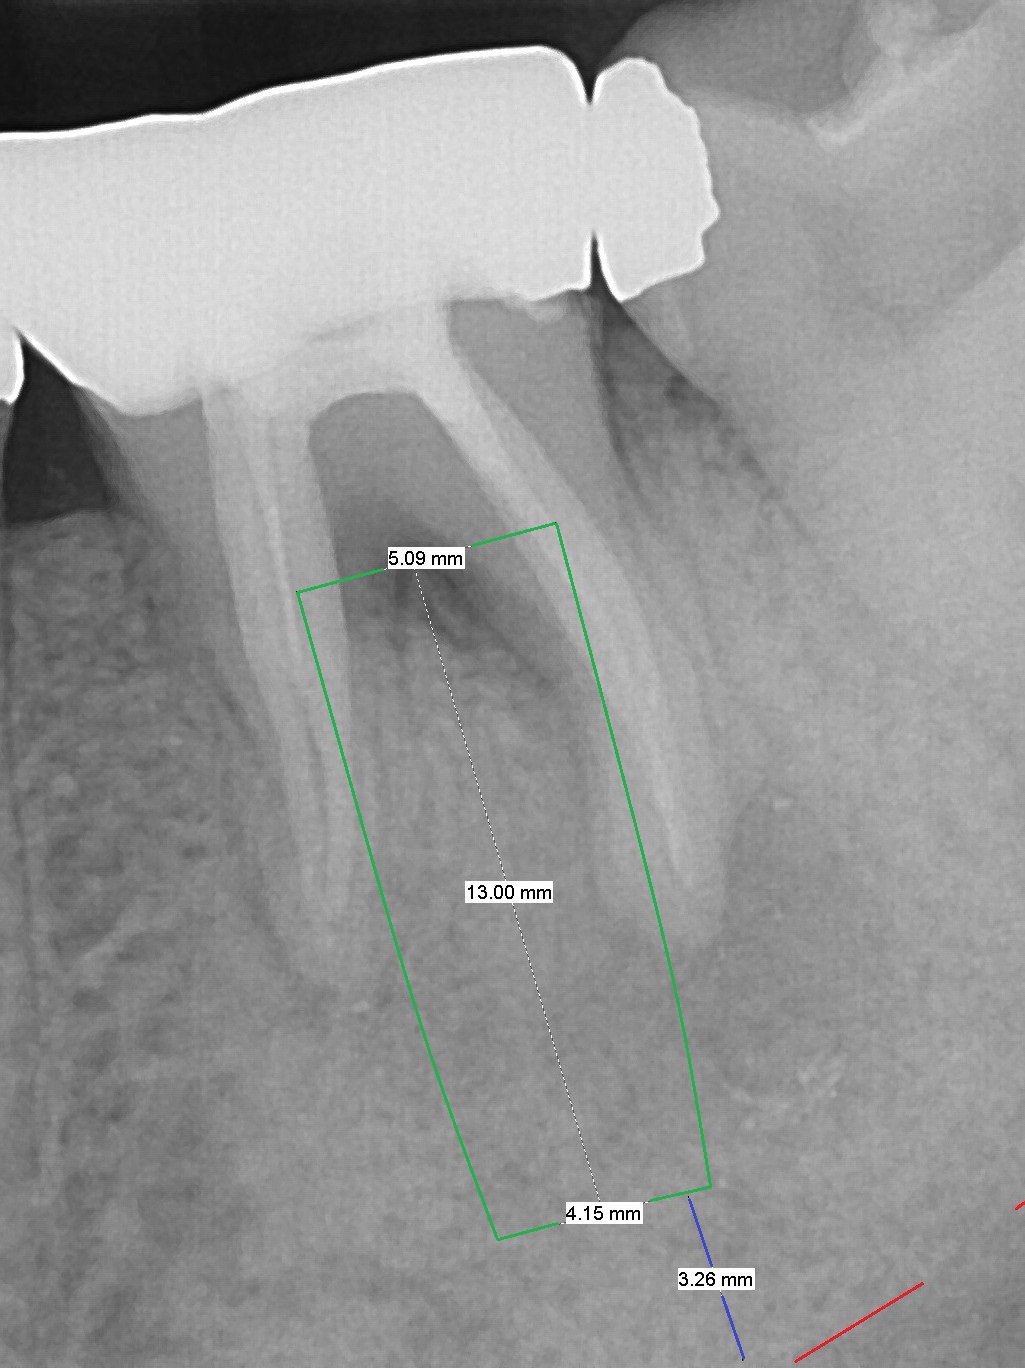

A 48-year-old woman has had mild discomfort at #19 four years post RCT (Fig.1). It appears that the tooth has 3 roots. The latter should help stabilize an implant placed in the septum (tripods). The affected tooth has large distal periapical radiolucency (Fig,2 *). There is localized swelling at the buccal furca. After debridement, treat the sockets with Clindamycin. Osteotomy will be slightly lingual, since the buccal plate is thinner than the lingual one. In addition, the buccal plate is most likely defective due to furca and periapical lesions. The longest IBS implant is going to be chosen unless the implant has to be placed deep due to furca destruction. In fact the patient has the tooth extracted in other office with socket preservation.